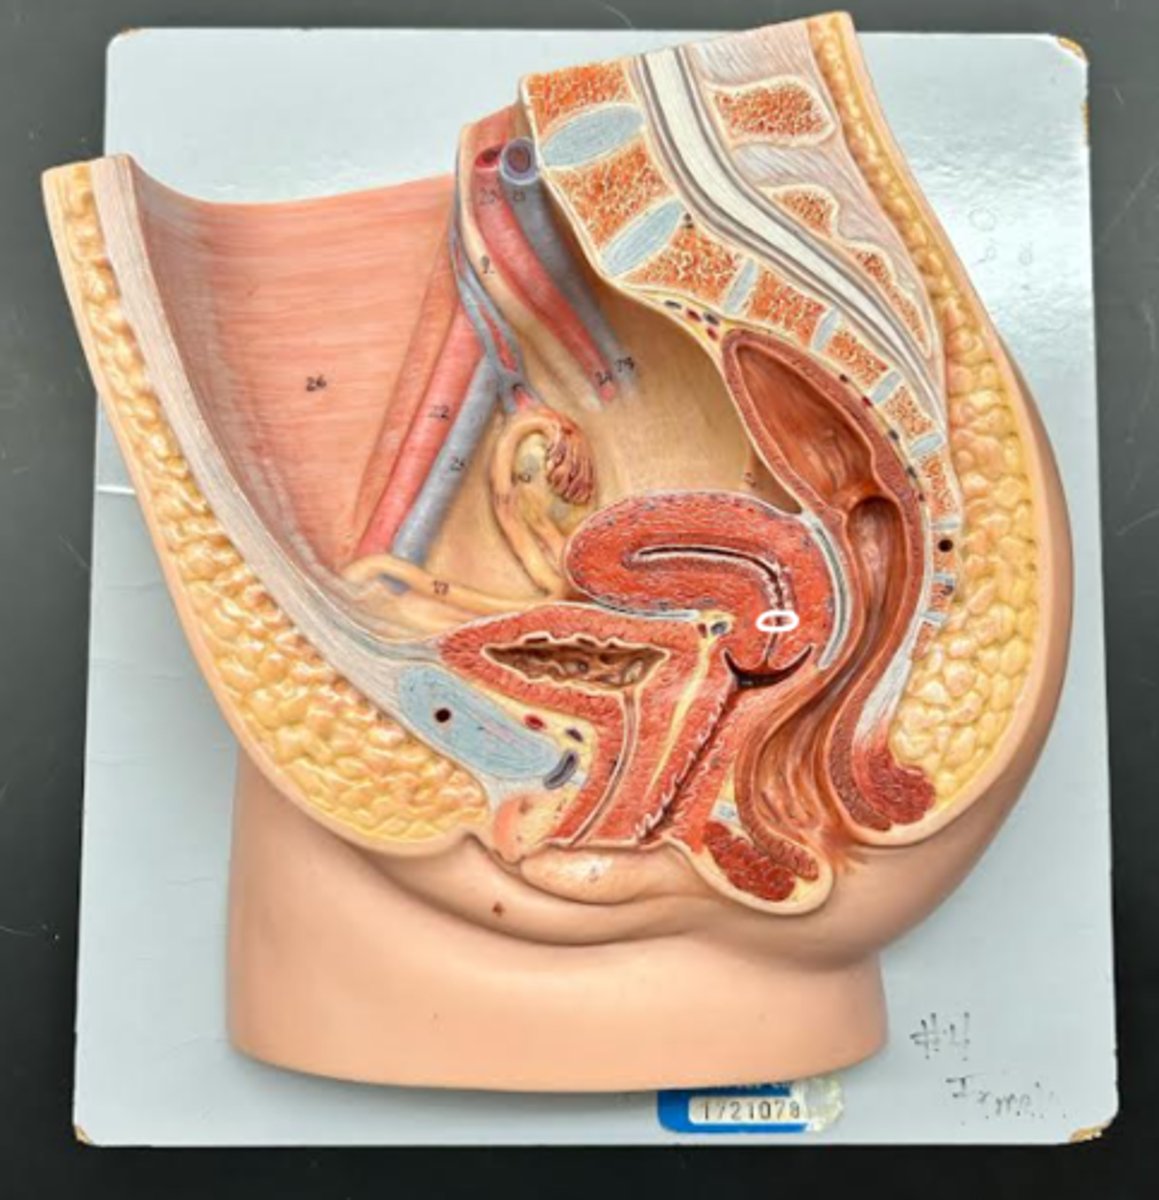

Vagina

Vaginal fornix

Ovary

Fallopian tube

Uterus

Fundus

Body of uterus

Cervix

right ovary

infundibulum

2

ampulla

3

isthmus

4

fundus